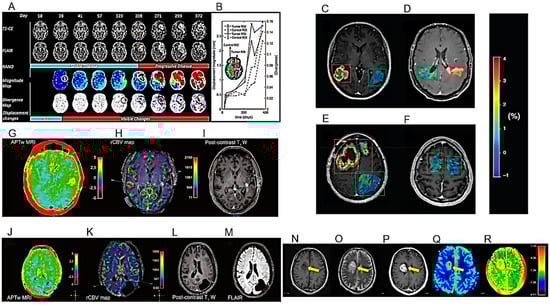

| Proposal of an an automated method to quantify the subtle deformations that occur in the peritumoral regions. | 229 MRI exams from 27 patients with histologically confirmed HGG. | [31] |

| APTw MRI imaging shows good scan–rescan reproducibility in healthy tissue and tumors. | 21 healthy volunteers and 6 glioma patients (4 GBs, 1 oligodendroglioma, 1 radiologically suspected LGG). | [32] |

| APTw MRI max values correlate positively with rCBVmax. | 40 adult patients, treated for histopathologically confirmed glioma (WHO grades II–IV). | [33] |

| APTw MRI mean values might be helpful in the differential diagnosis of HGGs and meningiomas or HGGs and LGGs. | Imaging data of 50 BTs confirmed by pathology. | [34] |

| CCA might help to distinguish PsP or RN from PD after RT. | 16 patients with a primary and 17 with a secondary BT. | [40] |

| SWI permits to identify haemorrhagic changes due to anti-VEGF drugs. | A case of pseudoprogression after ioRT and regorafenib therapy in a patient with anaplastic astrocytoma recurrence. | [41] |

| Use of the tissue permeability and microcirculation parameters Ktrans, Kep, IAUC to differentiate PT from TM. | 34 patients with HGG. | [43] |

| Features of conventional MRI and RT treatment such as radiation dose, marginal enhancement and isointense ADC-signal may be useful to distinguish between progressive disease and TIE. | HGG adult patients who were treated with chemo/RT and subsequently developed a new or increasing CE lesion on conventional follow-up MRI. | [44] |

| Unlike the quantitative measurements of DSC and DCE perfusion maps, their qualitative assessment has low inter-examinator agreement. | HGG patients who underwent re-resection of a new enhancing lesion on post-treatment 3T MR examination including DWI, DCE and DSC sequences. | [45] |